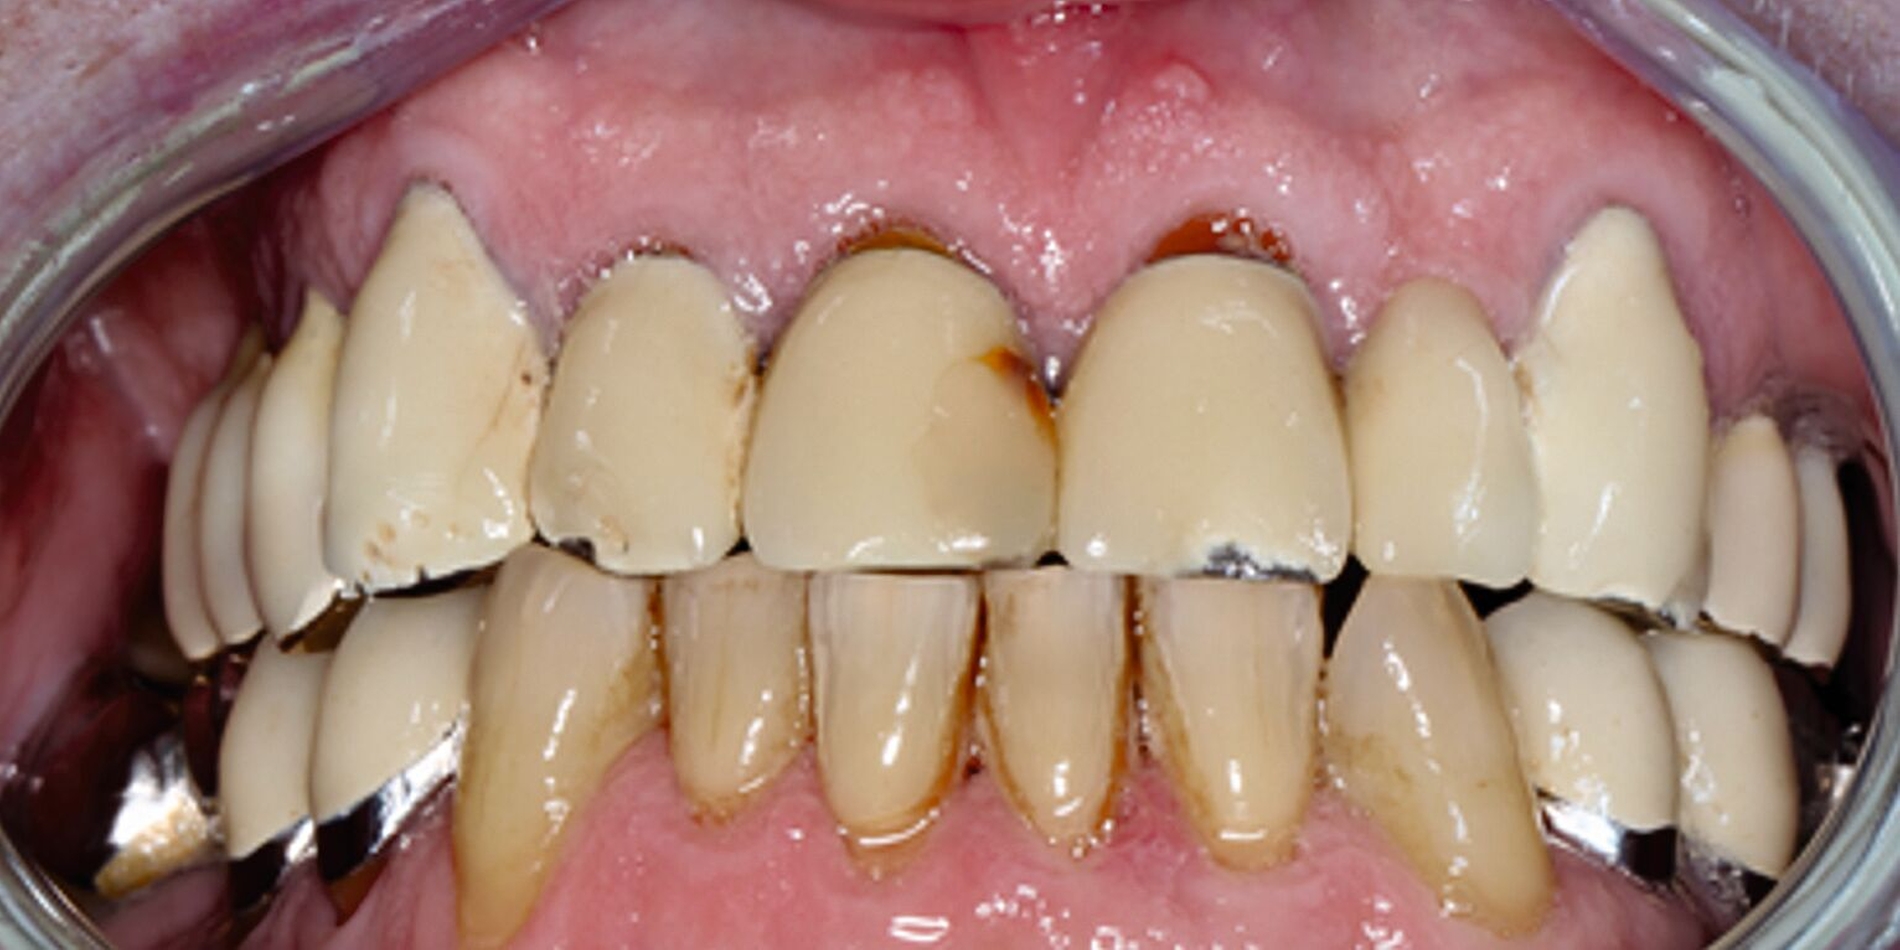

Der Patient stand unter der Dauermedikation von Metformin 500 mg, Ramipril 5 mg, Torasemid 10 mg, Metohexal 47,5 mg, Simvastatin 20 mg, Tamsulosin 0,4 mg und 3 mg Marcumar (INR 2,5–2,8) bei Zustand nach einer Bypass-Operation im Jahr 2019. Klinisch zeigten sich im Oberkiefer insuffiziente, verblockte und verblendete NEM-Kronen mit beidseitigen Gold-Extensionen distal, die über Geschiebe mit dem anterioren Anteil verschraubt waren (Abbildungen 1 und 2). Der Patient berichtete, dass die vorhandenen Kronen und Brücken 1984 eingesetzt worden seien.

Besonders auffällig war eine Dezementierung, die klinisch durch rechtsseitigen Druck und Zug mit einer Pinzette und daraufhin austretende Sulkusflüssigkeit in Regio 14 detektiert wurde. Da entsprechend des synoptischen Behandlungskonzepts [Naumann et al., 2010] bei prothetischer Neuversorgung eine gesamte Evaluation der Restpfeiler erfolgen muss, wurden zunächst die Kronen im Oberkiefer durch Schlitzen und Aufbiegen entfernt. Erst danach ließ sich deren Erhaltungswürdigkeit abschließend beurteilen.

So war der Zahn 14 tief kariös zerstört und nicht-erhaltungswürdig, was mit dem Bild der wahrscheinlich seit Längerem bestehenden Dezementierung korrelierte (Abbildung 3). Die Brücken im Unterkiefer wurden als suffizient befundet. Die Ruheschwebelage wurde mithilfe des Zielinsky-Zirkels auf 2 mm bestimmt. Parodontologisch zeigten sich stabile Verhältnisse. Ein Parodontaler Screening-Index (PSI) wurde erhoben (3-1-1-1-2-2). Der hier auffällige Zahn 14 wurde bereits zuvor beim klinischen Befund als nicht-erhaltungswürdig eingestuft und im Verlauf extrahiert.